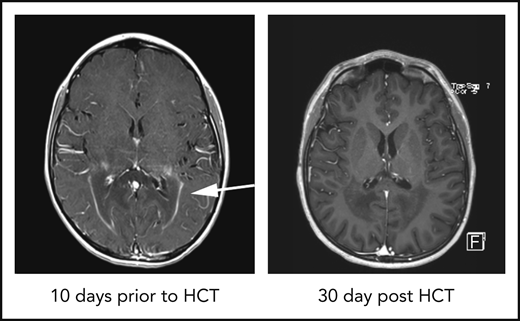

Adrenoleukodystrophy (ALD) is a rare X-linked peroxisomal disorder caused by mutations within the ABCD1 gene resulting in the accumulation of very long chain fatty within tissues, particularly the adrenal glands, testes, and the central nervous system (CNS).1 Most boys develop adrenal dysfunction at ages 4 to 7 years, and up to 40% of boys develop a severe demyelinating form of ALD, cerebral ALD (cALD), between ages 4 and 10 years (median 7 years).1 cALD is progressive, neurologically devastating, and fatal without intervention. The hallmarks of cALD disease manifestation are regions of demyelination observed on brain magnetic resonance imaging (MRI) that are associated with a “garland ring” of gadolinium contrast enhancement, often localized to the occipital–parietal region. Gadolinium enhancement indicates active blood-brain barrier (BBB) disruption.2 Only hematopoietic cell transplant (HCT) has been shown to halt neurologic progression, with the best outcomes when HCT is performed early in the disease process, although the mechanism of disease arrest by donor hematopoietic cells is unknown.3 Following HCT, the gadolinium enhancement resolves as soon as 28 days after transplant in some patients (Figure 1A), and it is thought that most patients will show gadolinium resolution by 100 days after HCT, indicating elimination of active neuroinflammation. The factors associated with gadolinium resolution are not known. Our goal was to evaluate gadolinium resolution in boys undergoing HCT for cALD and determine whether there were other biomarkers of disease or transplant characteristics that were associated with resolution.

Gadolinium resolution on brain MRI correlates with donor neutrophil recovery in cALD patients. (A) Example of a T1-weighted MRI showing a classic ring of gadolinium contrast (arrow; left panel). An MRI exhibiting complete gadolinium contrast resolution 30 days after HCT (right panel). (B) Percentage of patients having complete gadolinium resolution at the indicated time points after HCT. The blue columns represent patients with neutrophil recovery and single HCT, and the red columns represent patients who failed to engraft. (C) Day of neutrophil recovery for patients with contrast resolution at the indicated cumulative time points post-HCT. (D) Frequency of contrast resolution between patients who had ANC recovery ≤ 16 days (faster) vs >16 days (slower). (E) Frequency of contrast resolution in cALD patients with higher CD15 chimerism (70-100%) vs lower CD15 chimerism (<70%) at 60 days post-HCT. (F) Table of pre-HCT and HCT parameters with univariate analysis P values. Variables used in the multivariate analysis model are in bold type. All P values were derived using Fisher’s exact test.